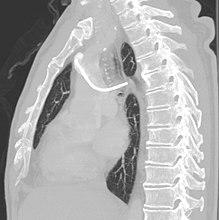

- Pneumothorax: Attempts to gain access to the subclavian vein or jugular vein can injure the lung, potentially causing a pneumothorax. If the pneumothorax is large enough, a chest tube might need to be placed. In experienced hands, the incidence of this complication is about 1% when accessing the subclavian vein. When accessing the jugular vein the pneumothorax rate is virtually nonexistent.